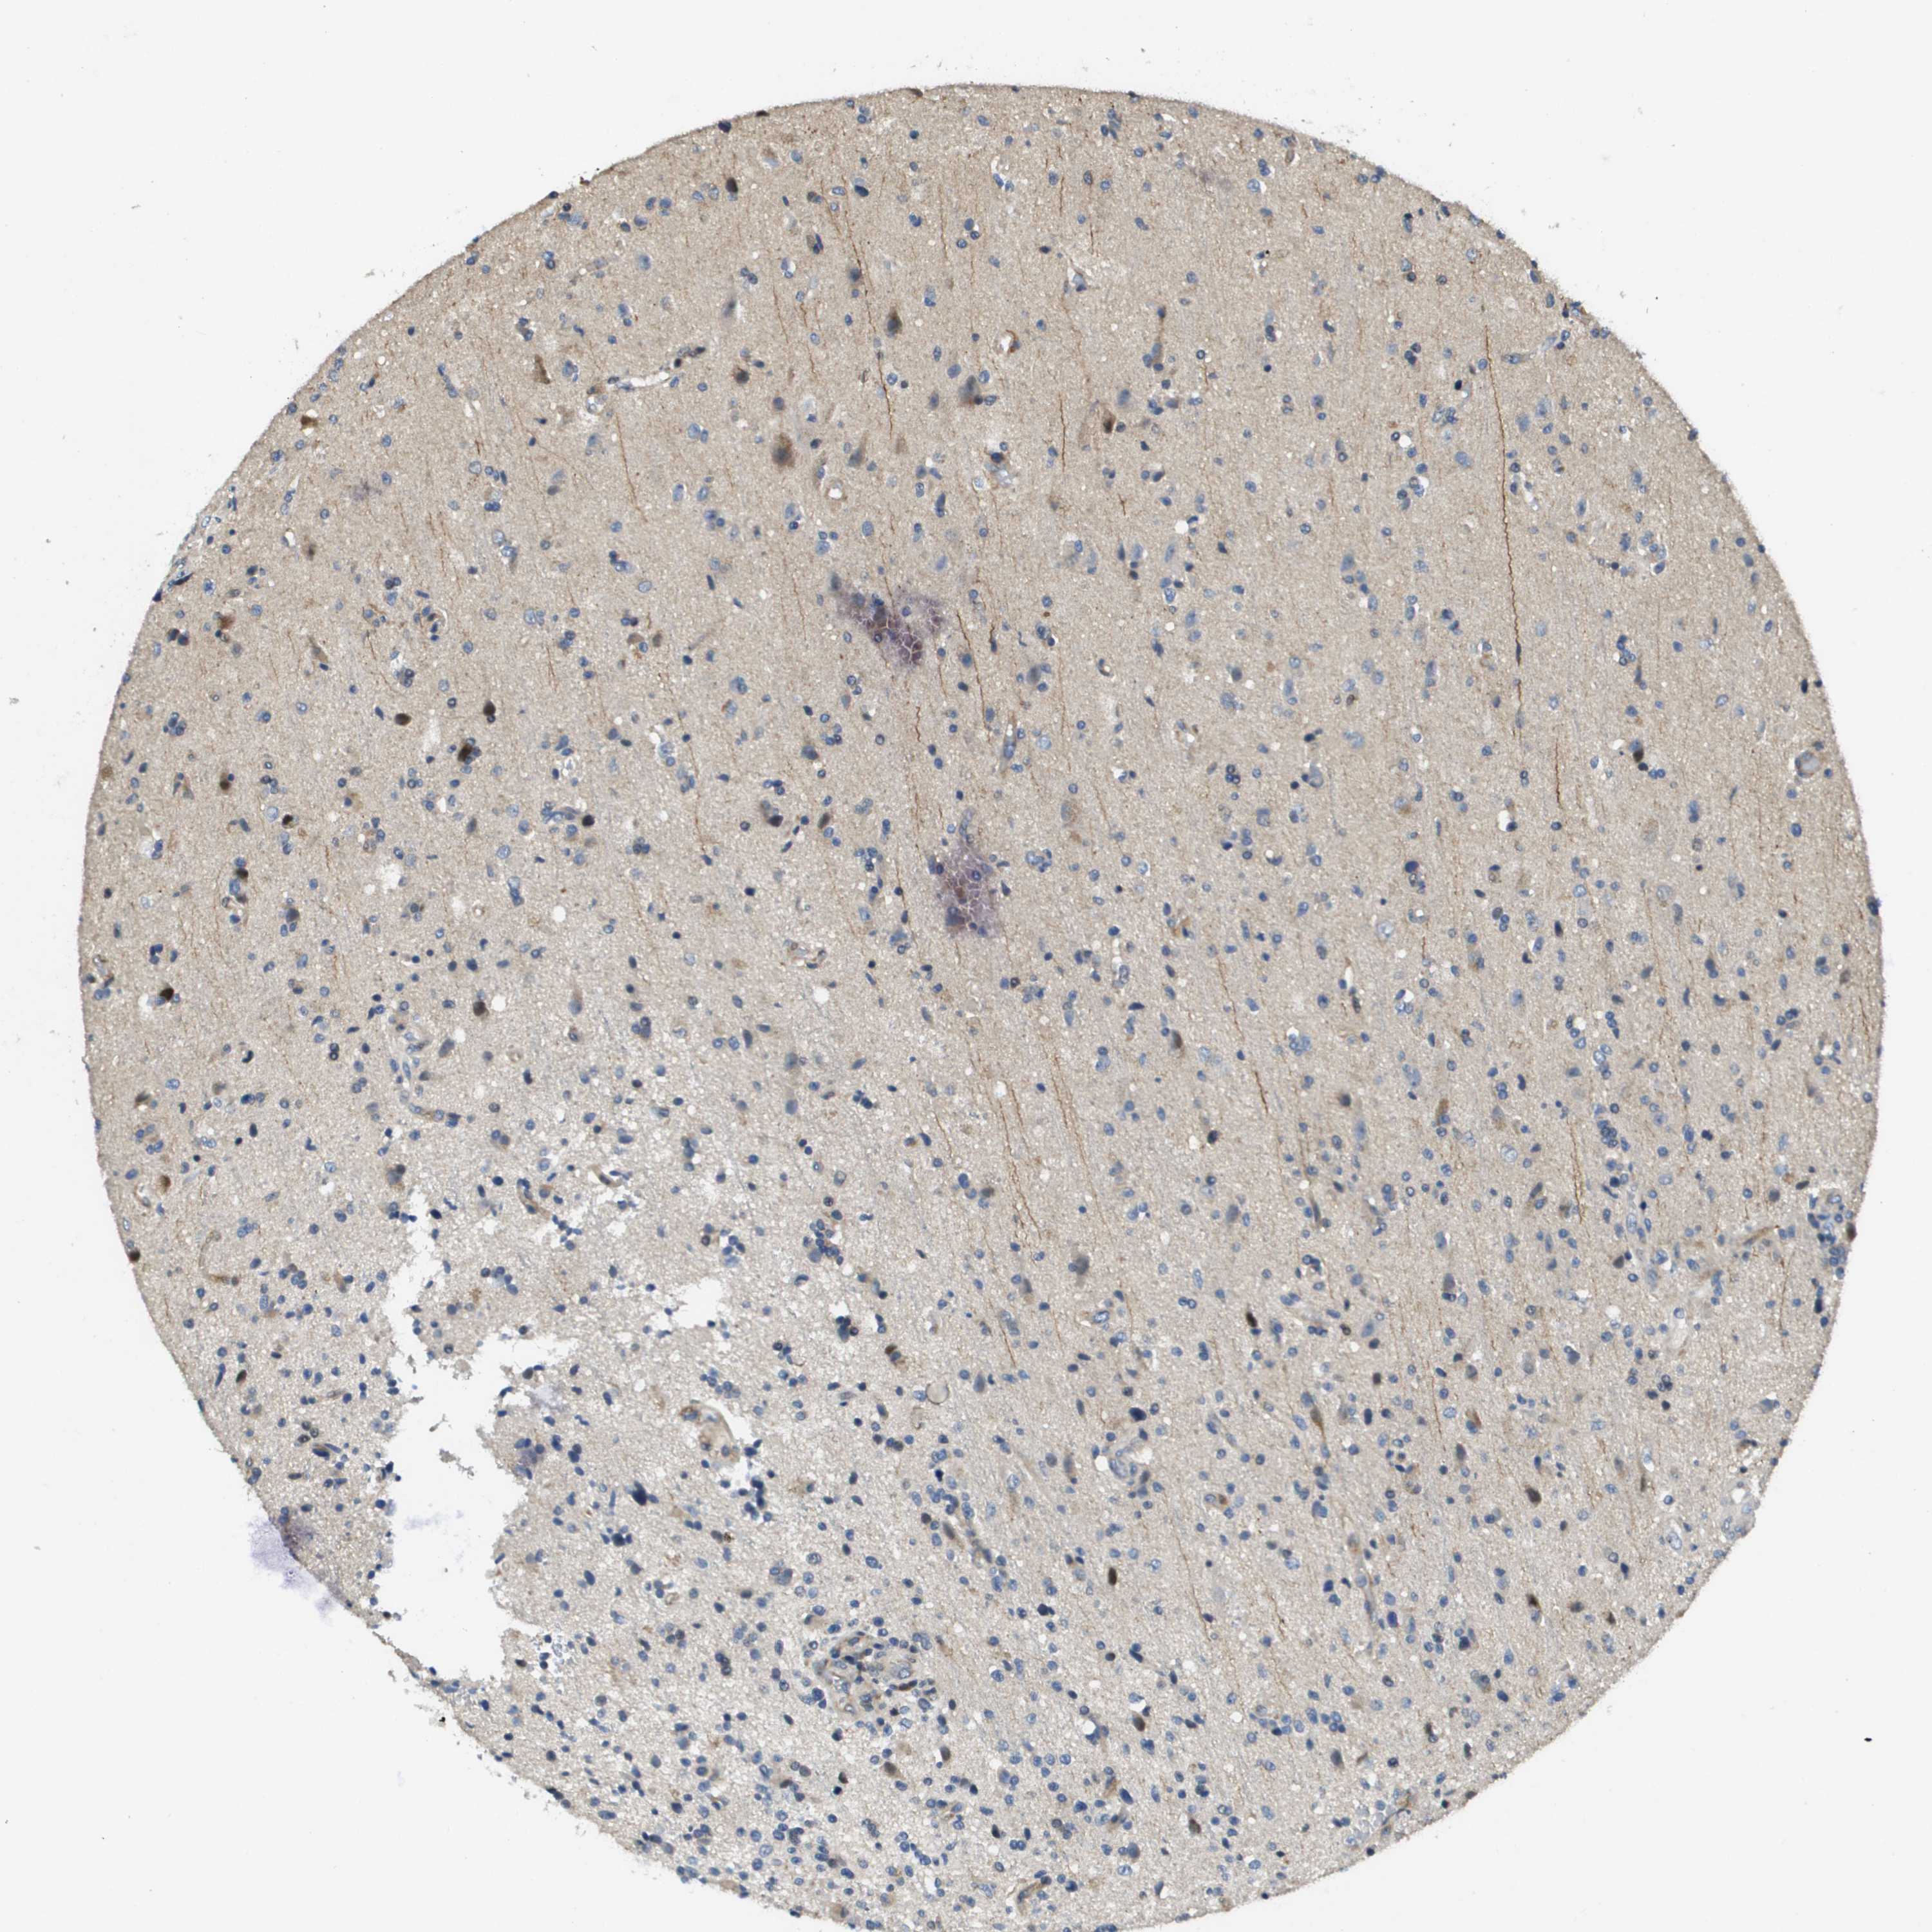

GLIOMA - Protein expressioni

A mouse-over function shows sample information and annotation data. Click on an image to view it in a full screen mode. Samples can be filtered based on level of antibody staining by selecting one or several of the following categories: high, medium, low and not detected. The assay and annotation is described here.

Note that samples used for immunohistochemistry by the Human Protein Atlas do not correspond to samples in the TCGA dataset.

Antibody stainingi

Antibody staining in the annotated cell types in the current human tissue is reported as not detected, low, medium, or high, based on conventional immunohistochemistry profiling in selected tissues. This score is based on the combination of the staining intensity and fraction of stained cells.

Each image is clickable and will lead to virtual microscopy that enables deeper exploration of all samples and also displays staining intensity scores, fraction scores and subcellular localization as well as patient and tissue information for each sample.

Antibody HPA017293

Staining

High

Medium

Low

Not detected

Intensity

Strong

Moderate

Weak

Negative

Quantity

>75%

75%-25%

<25%

None

Location

Nuclear

Cytoplasmic/membranous

Cytoplasmic/membranous,nuclear

Glioma, malignant, High grade

Glioma, malignant, Low grade